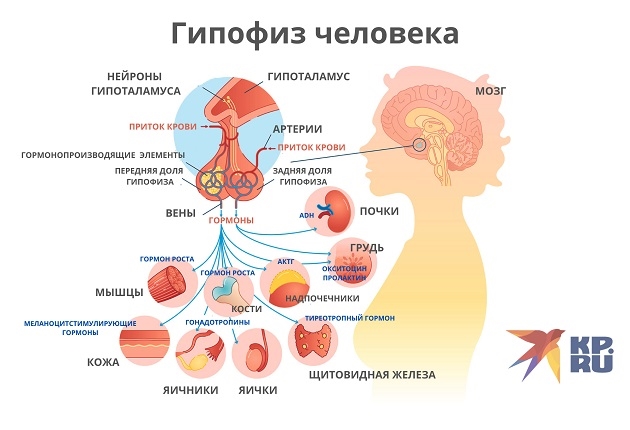

Как работает центр насыщения в гипоталамусе: визуальные иллюстрации